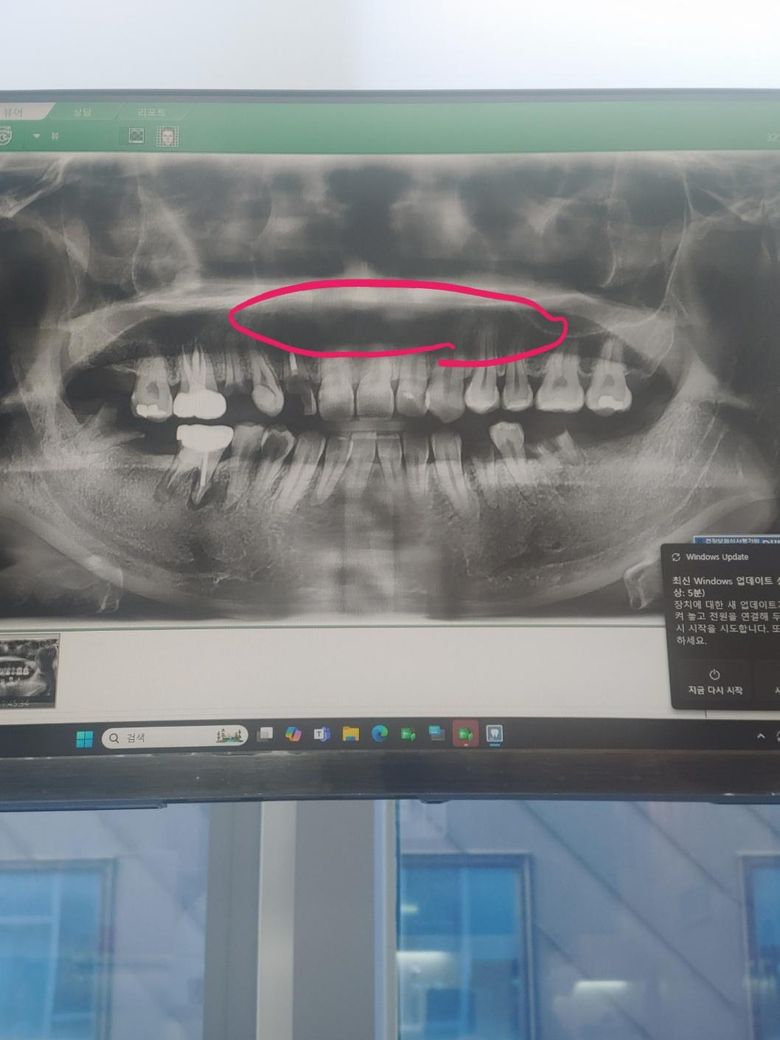

치아 파노라마 상에 앞니들 위에 부분이 검게 보이는데 뿌리랑 잇몸뼈가 녹은걸까요?

치아 파노라마 상에 앞니들 위에 부분이 검게 보이는데요 혹시 치아 뿌리랑 잇몸 뼈가 녹은걸까요...............?

파노라마 방사선 사진은 왜곡, 중첩 등이 많이 발생합니다. 위 파노라마 사진상에서 검은 부분은 입천장과 혀 등이 겹쳐서 그렇게 보이는 것이고 실제로 뼈가 녹거나 그렇지는 않았을 것입니다.

파노라마 상에서 검게 나타나는 부분이 모두 염증을 의미하지 않으며 해당부분은 염증은 아닙니다.

사진상의 오류일수도 잇고 연조직과 겹쳐보이면서 그렇게 보일수도 잇고 콧구멍이나 상악동같은 곳입니다.

치아 파노라마 상에 앞니들 위에 부분이 검게 보이는 경우 혹시 치아 뿌리랑 잇몸 뼈가 흡수되어 그림자져서 보입니다. 염증이 있을 가능성이 높으며, 치아 뿌리 주변에 염증이 생기면, 그 부위의 뼈가 흡수되어 검은 그림자로 나타날 수 있습니다.

보다 정확한 상태 확인을 위해서는 우선 치과에 방문하여 실제로 상태를 확인해보길 권합니다.

방사선 사진으로 해당 부위는 검게 보일 수 있습니다. 충치가 있어. 부러진 채 뿌리는 치근단 질환이 있을 가능성이 높아 보이나 방사선 사진으로는 정확한 확인이 어려워보입니다. 이런 경우에는 치근단 사진이나 CT 촬영을 통해서 확인을 할 수 있습니다.